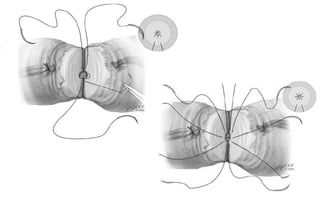

GranulomaCOMPARAÇÃO ENTRE TÉCNICAS

REVERSÃO DE VASECTOMIA

Aspectos TécnicosMobilização suficiente dos cotosThomas AJ, in Surgery for Male Infertility,  2006